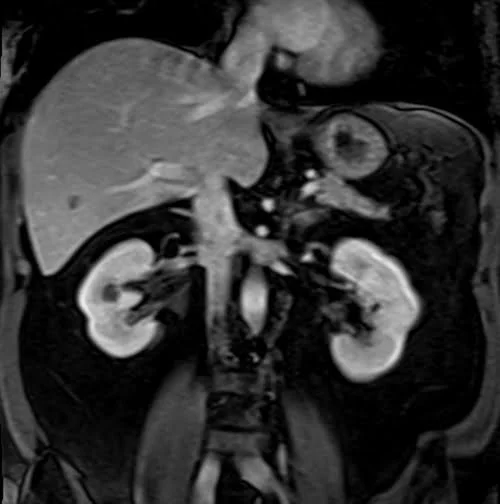

VIBE FAT SAT CORONAL POST CONTRAST SEQUENCE USED IN KIDNEYS IMAGING